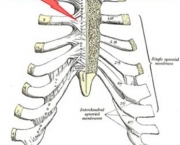

As dores da Costocondrite são causadas por uma inflamação da cartilagem que faz a ligação entre as costelas e osso do peito. Existem níveis dessa doença indo desde leve até uma irritação extremamente dolorosa. As pessoas que sofrem dessa doença chegam a definir a dor como uma sensação de queimadura intensa.

O diagnóstico da Costocondrite pode ser feito pelo médico através de pressão realizada sobre a área em que acontece o encontro das costelas e do osso do peito. Quando existe algum tipo de inflamação nessa região a causa mais comum é a Costocondrite. Em geral o médico realiza mais um teste para ter certeza de que não se trata de um problema cardíaco e outras doenças que também poderiam causar dores no peito.